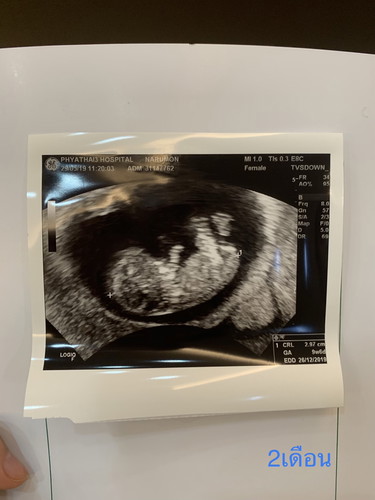

ครั้งแรกที่ซาวน้องยังเป็นก้อนกลมๆ ขอเรียกว่า ‘ตุ้มจิ๋ว’ คุณหมอนัดมาอีกทีเดือนหน้า ถ้าน้องไม่มีวิวัฒนาการ นั่นหมายถึงท้องลม.. ในระหว่างนี้ก็กังวลต่างๆ นาๆ พอเจอคุณหมอครั้งที่สอง คุณหมอบอกว่ามีสิทธิ์ที่จะท้องลม ไม่ก็ท้องนอกมดลูก เอาแล้วไงล่ะ.. ได้แต่ฟังแล้วจับมือกับคุณสามี จากนั้นคุณหมอให้ขึ้นเตียง เตรียมตัวซาวผ่านช่องคลอด คุณสามีก็มายืนข้างๆ ซักพักหมอก็ขยับอุปกรณ์ไปมา แล้วก็เจอกับตุ้มจิ๋วของแม่ (จิ๋วจริงๆ นะ 3เซน. เท่านั้นเอง) น้องมีแขน มีขา ที่สำคัญคือเสียงหัวใจน้องเต้นเร็วมาก วินาทีนั้นคือน้ำตาไหล คิดในใจอิหมอบิ๊วซะกลัวไปหมด ล้อเล่นค่ะ ? ตอนนั้นคิดแล้วว่า เราไม่ได้อยู่ตัวคนเดียวแล้วนะ มีสิ่งมีชีวิตที่หัวใจเต้นตุ๊บๆ ตั๊บๆ อยู่ด้วย ตอนนี้ได้ 22w แล้ว การเดินทางของพ่อแม่ลูกมาได้ครึ่งทางแล้ว อีกครึ่งทางเจอกันนะจ๊ะลูกจ๋า รักมากๆ เลย ❤️ สุดท้ายนี้อยากจะบอกว่า ลูกคือของขวัญที่ดีที่สุดของพ่อกับแม่นะ ปล.หวังว่าแม่ๆ ในนี้จะรู้สึกเหมือนกันนะคะ #ร่วมกิจกรรม #ความประทับใจ #ชิงเครื่องนึ่งขวดนม